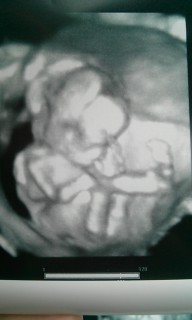

手足も長いし、指もちャんと5本見えるね♪と先生から言われました!この日は体育座りをしていてなかなか性別を教えてくれませんでした-。可愛すぎてもぉパパもベタ惚れです★

頭の後ろで手を組んで、すごくくつろいでいるように見えます!! この様子が私にそっくりだと友人たちに言われ、ウケました! (≧∀≦)

まだ性別は、はっきりわかりませんでしたが顔を手で覆っている姿が撮れました!次回は顔を見せてくれるといいです。大きさは14cmと書いてあります。